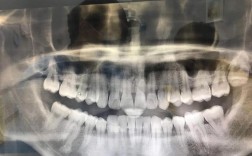

牙齿分析:

- 牙齿位置: 精确测量每颗牙齿在颌骨内的长、宽、高位置(如牙齿的唇/颊舌向倾斜、近远中向倾斜、垂直向位置)。

- 牙弓形态与大小: 分析上下牙弓的长度、宽度、形态是否与颌骨基骨协调。

- 牙齿拥挤度与间隙: 定量评估牙弓内是否存在拥挤或间隙。

- 咬合关系: 精确判断前牙覆合、覆盖程度,以及后牙的咬合关系(中性、近中、远中)。

- 提供三维信息: 它能同时显示骨骼、牙齿、软组织的前后、垂直、深度三个维度的关系,这是口内照片、模型或全景片无法完全替代的。